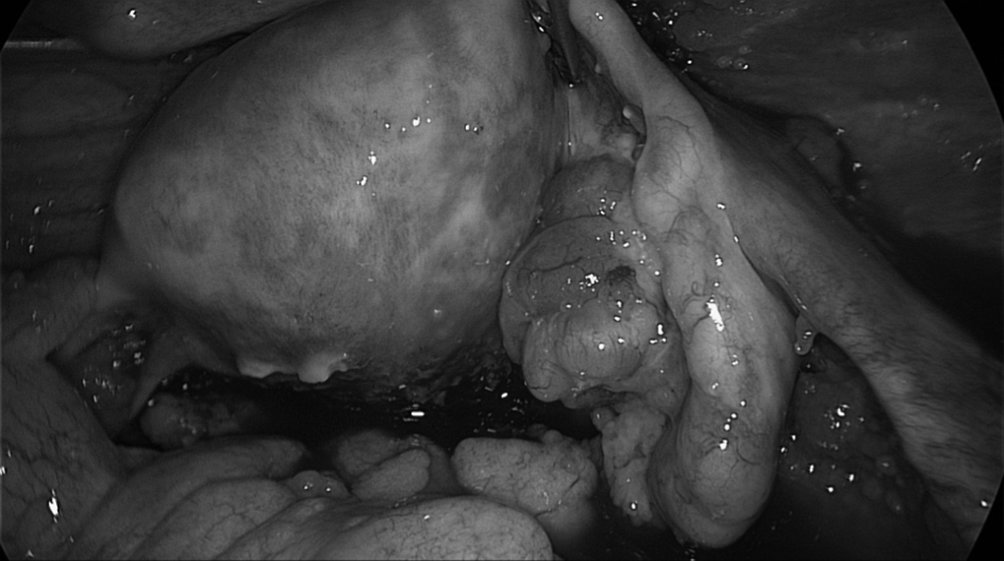

Figure 19.2 Vue en cœlioscopie du pelvis visualisant un utérus de taille normale avec au premier plan un ovaire de taille légèrement augmentée avec végétations exokystiques, présence d’une ascite dans le Douglas et implants péritonéaux en faveur d’une tumeur maligne de l’ovaire

Figure 19.2 Vue en cœlioscopie du pelvis visualisant un utérus de taille normale avec au premier plan un ovaire de taille légèrement augmentée avec végétations exokystiques, présence d’une ascite dans le Douglas et implants péritonéaux en faveur d’une tumeur maligne de l’ovaire.